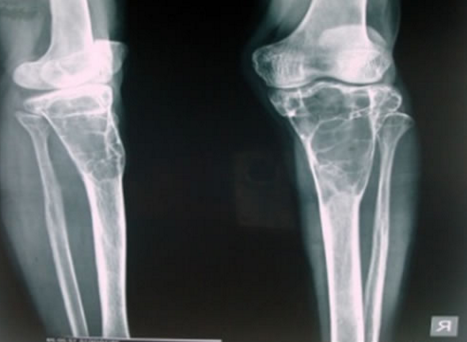

Quels sont les signes radiographiques d’une inflammation au niveau du coude ?

Quelle est la 1ère chose à rechercher lors d’une inflammation du coude sur une radiographie ?

Fracture de la tête radiale